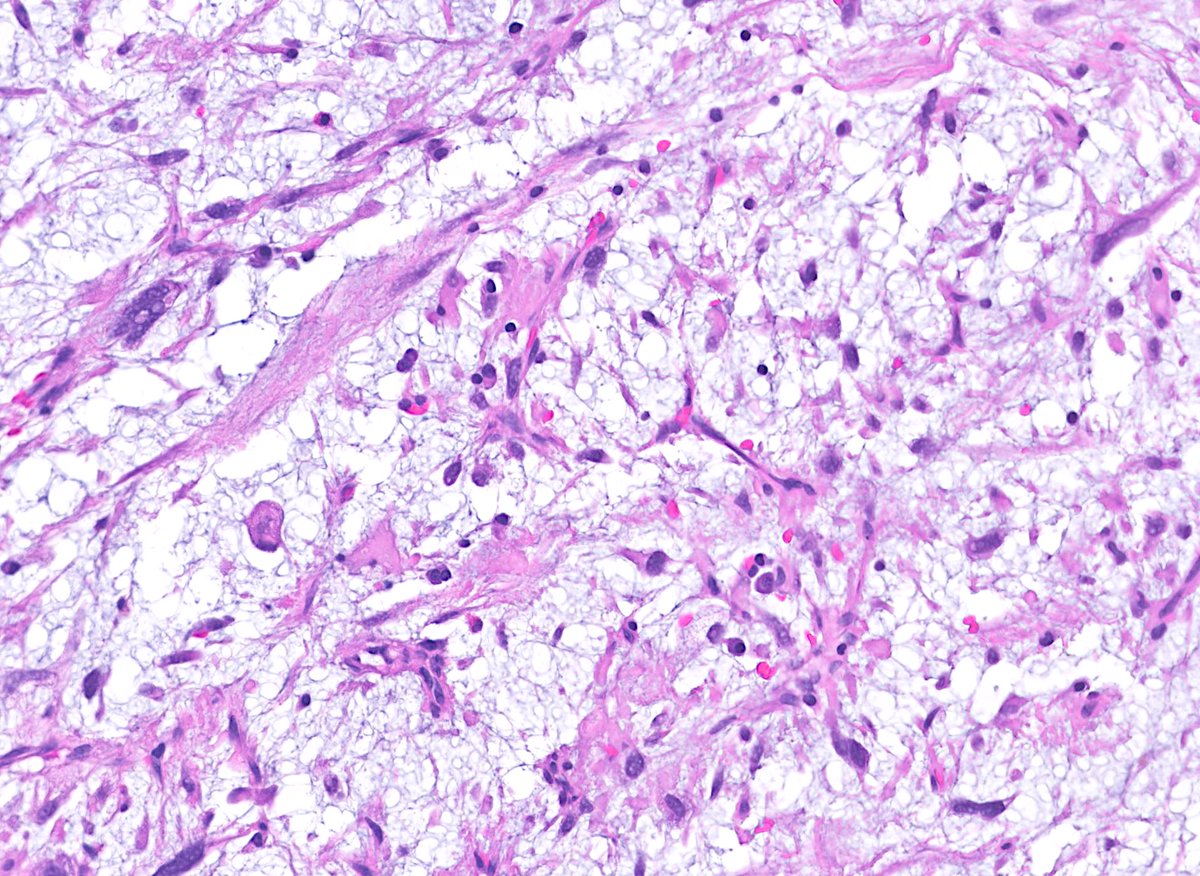

From mentors to mentees, our team is shining at #USCAP2025 in Boston! Faculty and residents are making an impact through research, collaboration, and a shared passion for pathology. Proud to see our department so well represented!